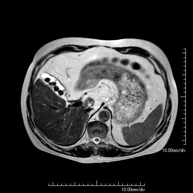

- RM Abdomen

Prueba diagnóstica no invasiva que consiste en la obtención de imágenes de alta definición anatómica del abdomen mediante el empleo de un campo electromagnético y ondas de radio (con un emisor y un receptor). No utiliza radiación ionizante. En esta exploración se incluyen el hígado, páncreas, bazo, vía biliar, vesícula biliar,Entero-RM glándulas suprarrenales, riñones, aorta abdominal, vena cava inferior, estómago, duodeno,…En ocasiones se deberá emplear contraste paramagnético (Gadolinio) para caracterizar las lesiones.

Prueba diagnóstica no invasiva que consiste en la obtención de imágenes de alta definición anatómica del abdomen mediante el empleo de un campo electromagnético y ondas de radio (con un emisor y un receptor). No utiliza radiación ionizante. En esta exploración se incluyen el hígado, páncreas, bazo, vía biliar, vesícula biliar, glándulas suprarrenales, riñones, aorta abdominal, vena cava inferior, estómago, duodeno, etc. En ocasiones se deberá emplear contraste paramagnético (Gadolinio) para caracterizar las lesiones.